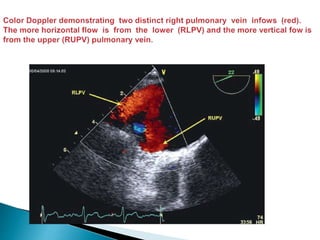

 Evaluation of the right sided veins is usually straight forward.

 From the mid esophageal 4 chambers view the probe is rotated to the right (with the

image sector angle at 0–30° and depth at about 10 cm) such that the inter-atrial septum is

horizontal and in the centre of the screen .

 Color Doppler is added to the left side of the screen and the probe is advanced slowly

until 2 distinct pulmonary infows are seen ; the more horizontal flow is from the RLPV and the

more vertical fow is from the RUPV.

 The RUPV can also be seen by maintaining the probe depth, rotating the image sector

plane to the bicaval view at 80–120° , and then manually rotating the probe clockwise/to the

right .

 This latter view of the RUPV is especially useful in patients’ with atrial septal defects (ASD)

when excluding anomalous pulmonary venous drainage (most commonly the RUPV) and

when assessing the distance betweenthe rim of the ASD and the RUPV prior to considering

percutaneous closure.